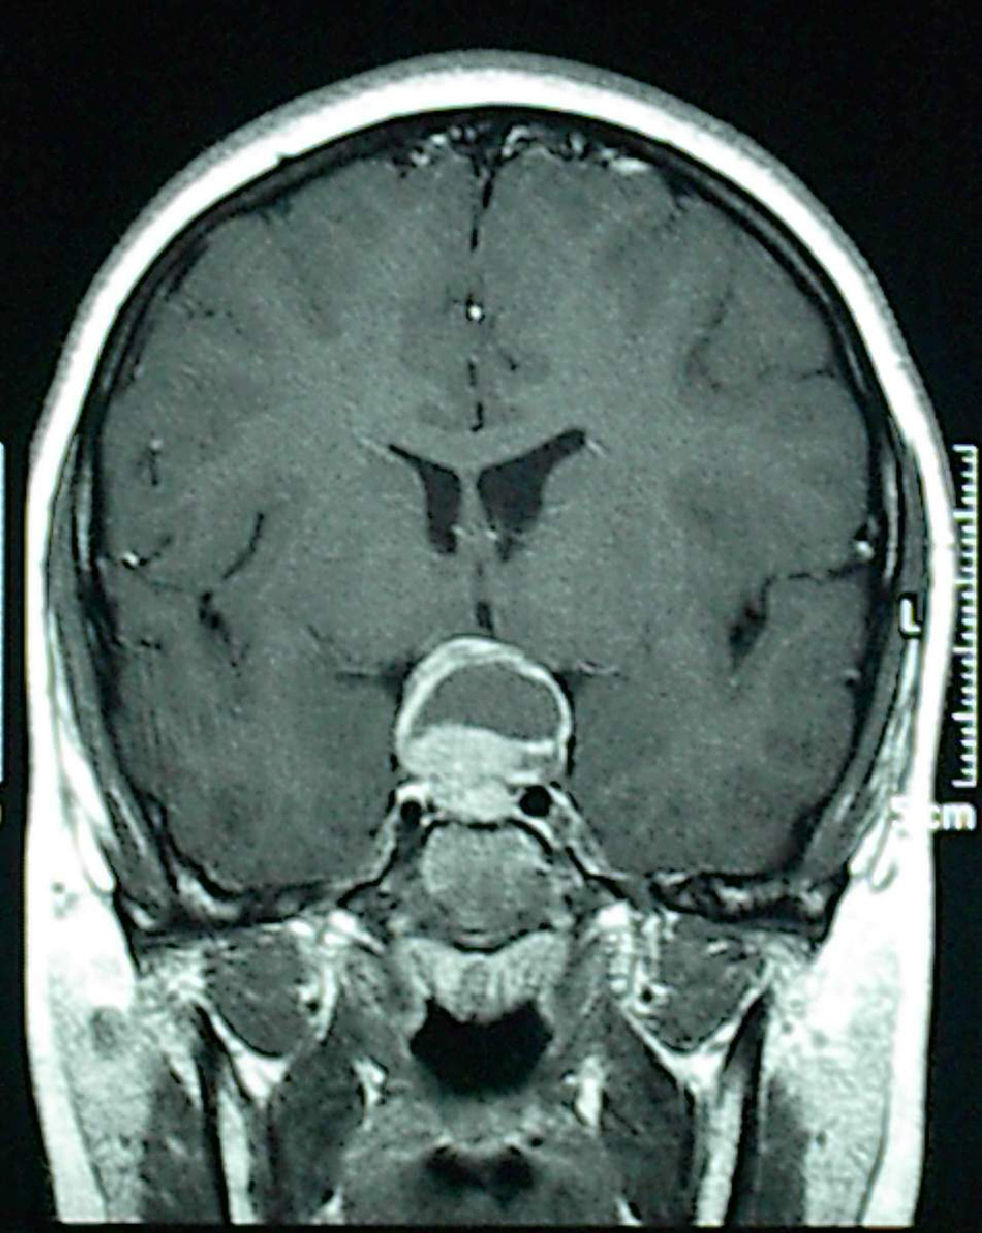

Four patients were successfully treated at the endocrinology department: 3 prolactinomas with the dopamine agonist cabergoline, while the patient with pituitary hyperplasia received levothyroxine. A 13-year-old boy complaining of headache underwent surgery with no prior hormone testing because neuroimaging revealed a lesion suspected to be craniopharyngioma because of its cystic appearance and large suprasellar extension (Fig. 1). The pathological laboratory diagnosed prolactinoma, and the cystic area was due to tumor apoplexy. The three patients with medically treated prolactinomas, all of them aged 13 years, were two pubertal girls complaining of isolated galactorrhea and with adenomas less than 10mm in size, and a boy reporting headache for the past few months and who had another cystic macroadenoma. Medical history of males included no evidence of endocrine disease that could have allowed for earlier diagnosis; they had not started puberty, and one of them showed mild bilateral gynecomastia 15mm in diameter, which could be considered physiological at this age.

Although adenomas are rare in children, prolactinoma should mandatorily be ruled out because it responds to medical treatment. Prolactinoma mainly occurs in children older than 12 years, but has also been reported in prepubertal children. A simple prolactin measurement higher than 200ng/mL diagnoses the tumor. Thus, when any sellar or parasellar mass is found, even in prepubertal children and regardless of radiographic appearance, prolactin levels should be measured before considering surgery.2–5,8,9 Adenomas may be confused with craniopharyingiomas, which may also have a sellar origin. Although the former are usually solid and the latter cystic, long-standing adenomas may grow and have cystic areas due to tumor apoplexy (tumor necrosis or hemorrhage).10–12 In our series, while pubertal females were quickly diagnosed based on galactorrhea, males had no symptoms of hypogonadism (because pubertal delay is only considered to be pathological from the age of 14 years), consulted for headache, and had large macroadenomas with cystic areas at onset.